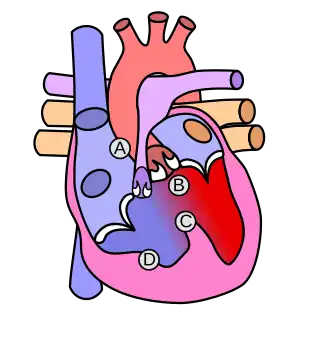

| Diagram of a healthy heart and one with tetralogy of Fallot | |

Tetralogy of Fallot (TOF), formerly known as Steno-Fallot tetralogy,[9] is a congenital heart defect characterized by four specific cardiac defects.[4] Classically, the four defects are:[4]

- Pulmonary stenosis, which is narrowing of the exit from the right ventricle;

- A ventricular septal defect, which is a hole allowing blood to flow between the two ventricles;

- Right ventricular hypertrophy, which is thickening of the right ventricular muscle; and

- an overriding aorta, which is where the aorta expands to allow blood from both ventricles to enter.

Four malformations

"Tetralogy" denotes four parts, here implying the syndrome's four anatomic defects.[2] This is not to be confused with the similarly named teratology, a field of medicine concerned with abnormal development and congenital malformations (including tetralogy of Fallot). Below are the four heart malformations that present together in tetralogy of Fallot:

| Pulmonary Infundibular Stenosis | A narrowing of the right ventricular outflow tract. It can occur at the pulmonary valve (valvular stenosis) or just below the pulmonary valve (infundibular stenosis).[4] Infundibular pulmonic stenosis is mostly caused by the overgrowth of the heart muscle wall (hypertrophy of the septoparietal trabeculae),[42] however, the events leading to the formation of the overriding aorta are also believed to be a cause. The pulmonic stenosis is the major cause of the malformations, with the other associated malformations acting as compensatory mechanisms to the pulmonic stenosis.[43] The degree of stenosis varies between individuals with TOF and is the primary determinant of symptoms and severity. This malformation is infrequently described as sub-pulmonary stenosis or subpulmonary obstruction.[44] |

| Overriding aorta | An aortic valve with biventricular connection, that is, it is situated above the ventricular septal defect and connected to both the right and the left ventricle. The degree to which the aorta is attached to the right ventricle is referred to as its degree of "override." The aortic root can be displaced toward the front (anteriorly) or directly above the septal defect, but it is always abnormally located to the right of the root of the pulmonary artery. The degree of override is extremely variable, with 5–95% of the valve being connected to the right ventricle.[42] |

| Ventricular septal defect (VSD) | A hole between the two bottom chambers (ventricles) of the heart. The defect is centered around the most superior aspect of the ventricular septum (the outlet septum), and in the majority of cases is single and large. In some cases, thickening of the septum (septal hypertrophy) can narrow the margins of the defect.[42] |

| Right ventricular hypertrophy | The right ventricle is more muscular than normal, causing a characteristic boot-shaped (coeur-en-sabot) appearance as seen by chest X-ray. Due to the misarrangement of the external ventricular septum, the right ventricular wall increases in size to deal with the increased obstruction to the right outflow tract. This feature is now generally agreed to be a secondary anomaly, as the level of hypertrophy tends to increase with age.[45] |